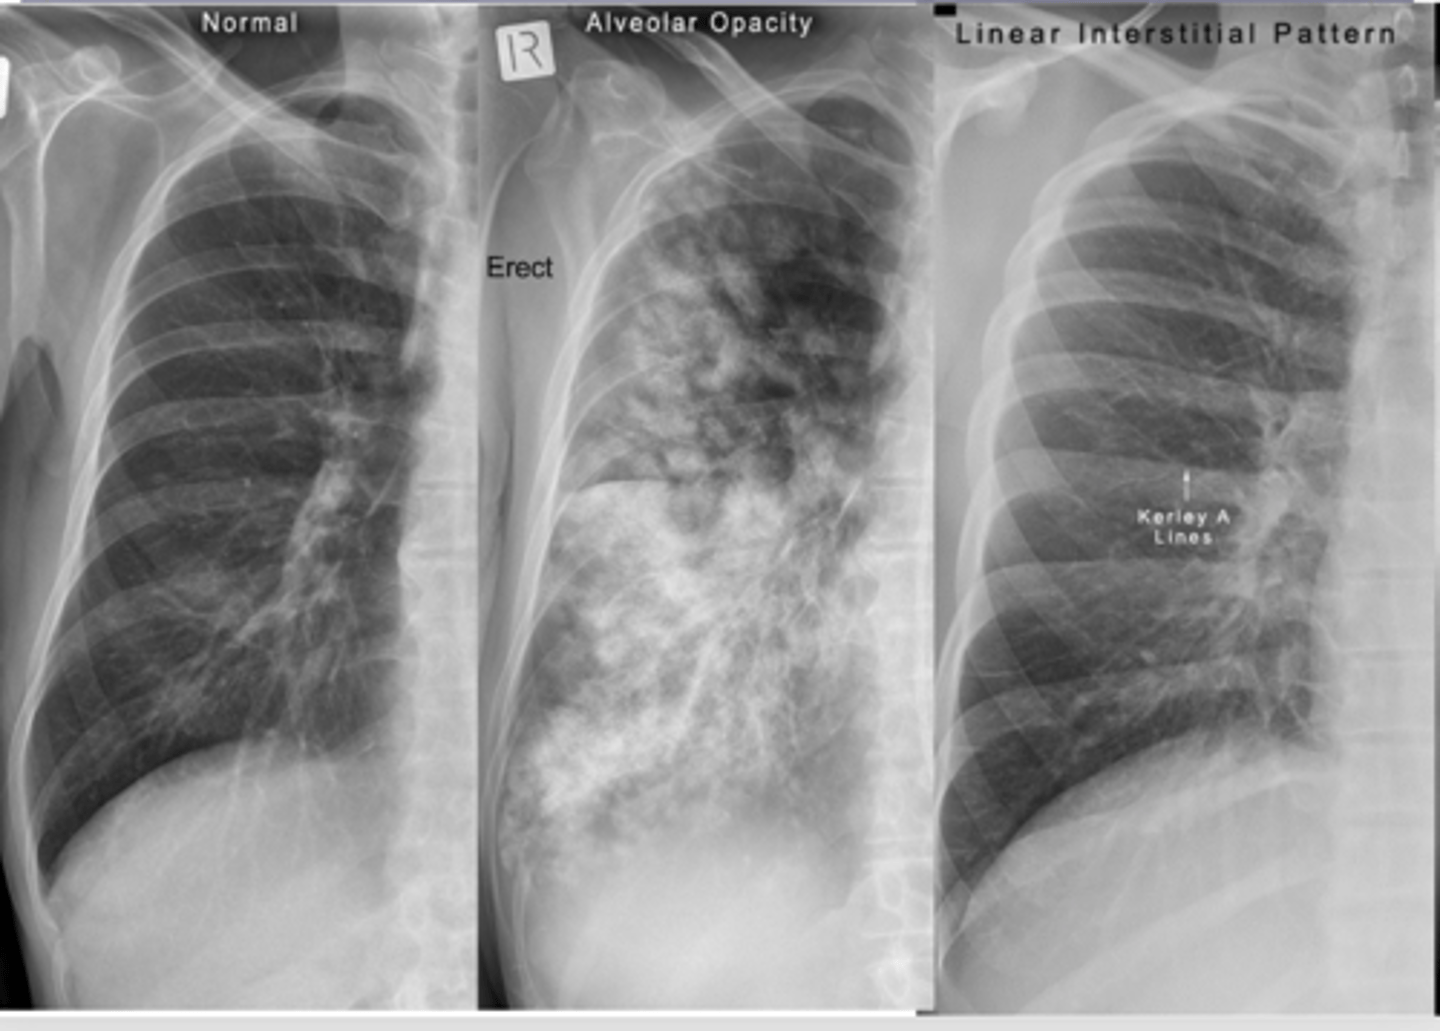

What are kerley A and B lines?

•Kerley A lines are linear opacities extending from the periphery to the hila caused by distention between peripheral and central lymphatics

•Kerley B lines are small, horizontal, peripheral straight lines demonstrated at the lung bases that represent thickened interlobular septa on CXR.

<p>•Kerley A lines are linear opacities extending from the periphery to the hila caused by distention between peripheral and central lymphatics</p><p>•Kerley B lines are small, horizontal, peripheral straight lines demonstrated at the lung bases that represent thickened interlobular septa on CXR.</p>

What do interstitial infiltrates look like and what are some causes? IS this sign specific or non specific?

caused by acute and chronic disease processes that affect the tissue outside of the alveoli.

Interstitial processes are usually diffuse & are seen as thin white lines. May appear honeycombed (reticular)

Interstitial infiltrates are nonspecific as they can be caused by many processes such as CHF, pulmonary fibrosis, collagen vascular diseases, etc.

<p>caused by acute and chronic disease processes that affect the tissue outside of the alveoli.</p><p>Interstitial processes are usually diffuse &amp; are seen as thin white lines. May appear honeycombed (reticular)</p><p>Interstitial infiltrates are nonspecific as they can be caused by many processes such as CHF, pulmonary fibrosis, collagen vascular diseases, etc.</p>

What are linear interstitial infiltrates also called? What is this sign commonly associated with?

Kerley lines --> interstitial pulm edema

<p>Kerley lines --&gt; interstitial pulm edema</p>